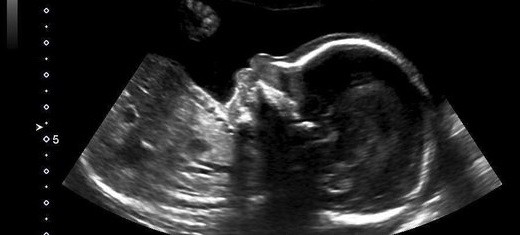

Nicole Kim, la madre de este particular bbé, encontró este inspirador mensaje en la ecografía de la semana 20: un pulgar para arriba.

En una entrevista con el Calgary Herald, Kim contó también que el técnico de la clínica de Calgary donde hizo la ecografía le dio rápidamente al zoom y tomó la foto cuando vio al bebé con el pulgar levantado.